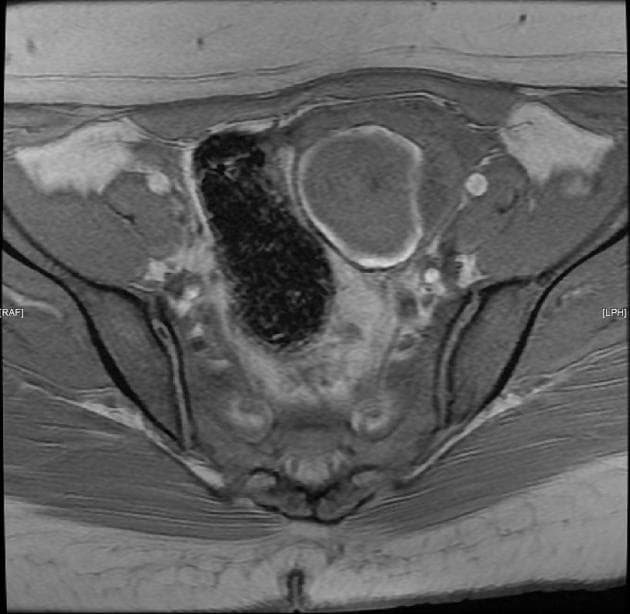

- Tổn thương dạng nang lớn ở vùng chậu bụng bên phải, trên cộng hưởng từ (MRI) tổn thương này tăng tín hiệu ở chuỗi xung T1 và T2, có vách ngăn nội tại.

- "U lạc nội mạc tử cung thường biểu hiện là các nang buồng trứng đơn hoặc đa ngăn, có tăng tín hiệu đồng nhất trên cả chuỗi xung T1 và T2 do chứa sản phẩm máu mạn tính."

- "Dấu hiệu chấm tối trên T2 (T2 shading) trong lòng nang là đặc điểm điển hình của u lạc nội mạc, do lắng đọng hemosiderin đậm đặc."

- "Vách ngăn nội tại và dày thành nang dạng nốt cho thấy tình trạng mạn tính hoặc nguy cơ chuyển ác, cần theo dõi sát."

U lạc nội mạc tử cung, còn gọi là 'nang sô cô la', là một dạng lạc nội mạc tử cung khi mô nội mạc tử cung lạc chỗ bám vào buồng trứng và xuất huyết theo chu kỳ. Trên cộng hưởng từ (MRI), u lạc nội mạc thường có tín hiệu tăng trên cả chuỗi T1 và T2 do chứa máu cũ. Hiện tượng 'mờ tín hiệu trên T2' (T2 shading) – khi tín hiệu giảm dần trên hình T2 – rất gợi ý cho chẩn đoán u lạc nội mạc. Các chẩn đoán phân biệt bao gồm nang buồng trứng xuất huyết, u nang tuyến mề và u tuyến nang nhầy. Tuy nhiên, tín hiệu T1 tăng rõ rệt và vách ngăn nội tại làm tăng khả năng u lạc nội mạc. Chẩn đoán chính xác rất quan trọng để định hướng điều trị, bao gồm điều trị nội tiết hoặc phẫu thuật cắt bỏ, đặc biệt ở bệnh nhân vô sinh hoặc đau vùng chậu mạn tính.